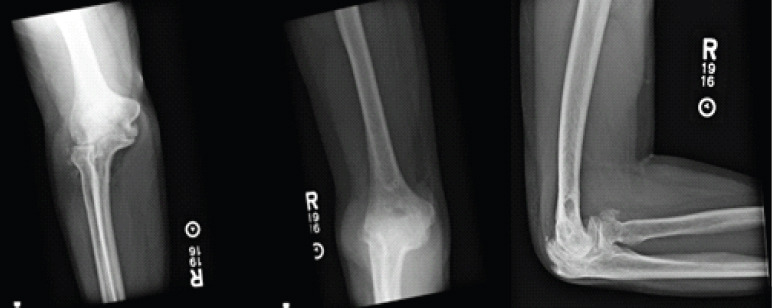

Case report: We report a case of a 50-year-old male who presented after the development of post-traumatic arthritis of the elbow after multiple prior surgeries. He was treated with an interpositional arthroplasty using an Achilles tendon graft and allowed immediate range of motion as tolerated in a hinged elbow brace without the use of any form of distraction external fixation. At his final follow-up, he has significantly improved pain, range of motion, and patient-reported Visual Analog Scale , American shoulder and elbow surgeons, mayo elbow performance score, and disabilities of the arm, shoulder and hand scores.

Conclusion: This case report demonstrated that interpositional arthroplasty is a viable option for managing post-traumatic elbow osteoarthritis in young patients and with good ligamentous stability, immediate protected range of motion, as tolerated, can lead to excellent outcomes.